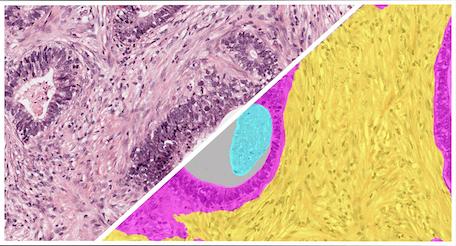

Breast IHC Tumor Tissue Detection

The Breast IHC Tumor Detection App is a pre-trained HALO AI classifier designed to detect, segment, and quantify tumor and other area across hematoxylin and DAB-stained whole-slide digital images of breast cancer.